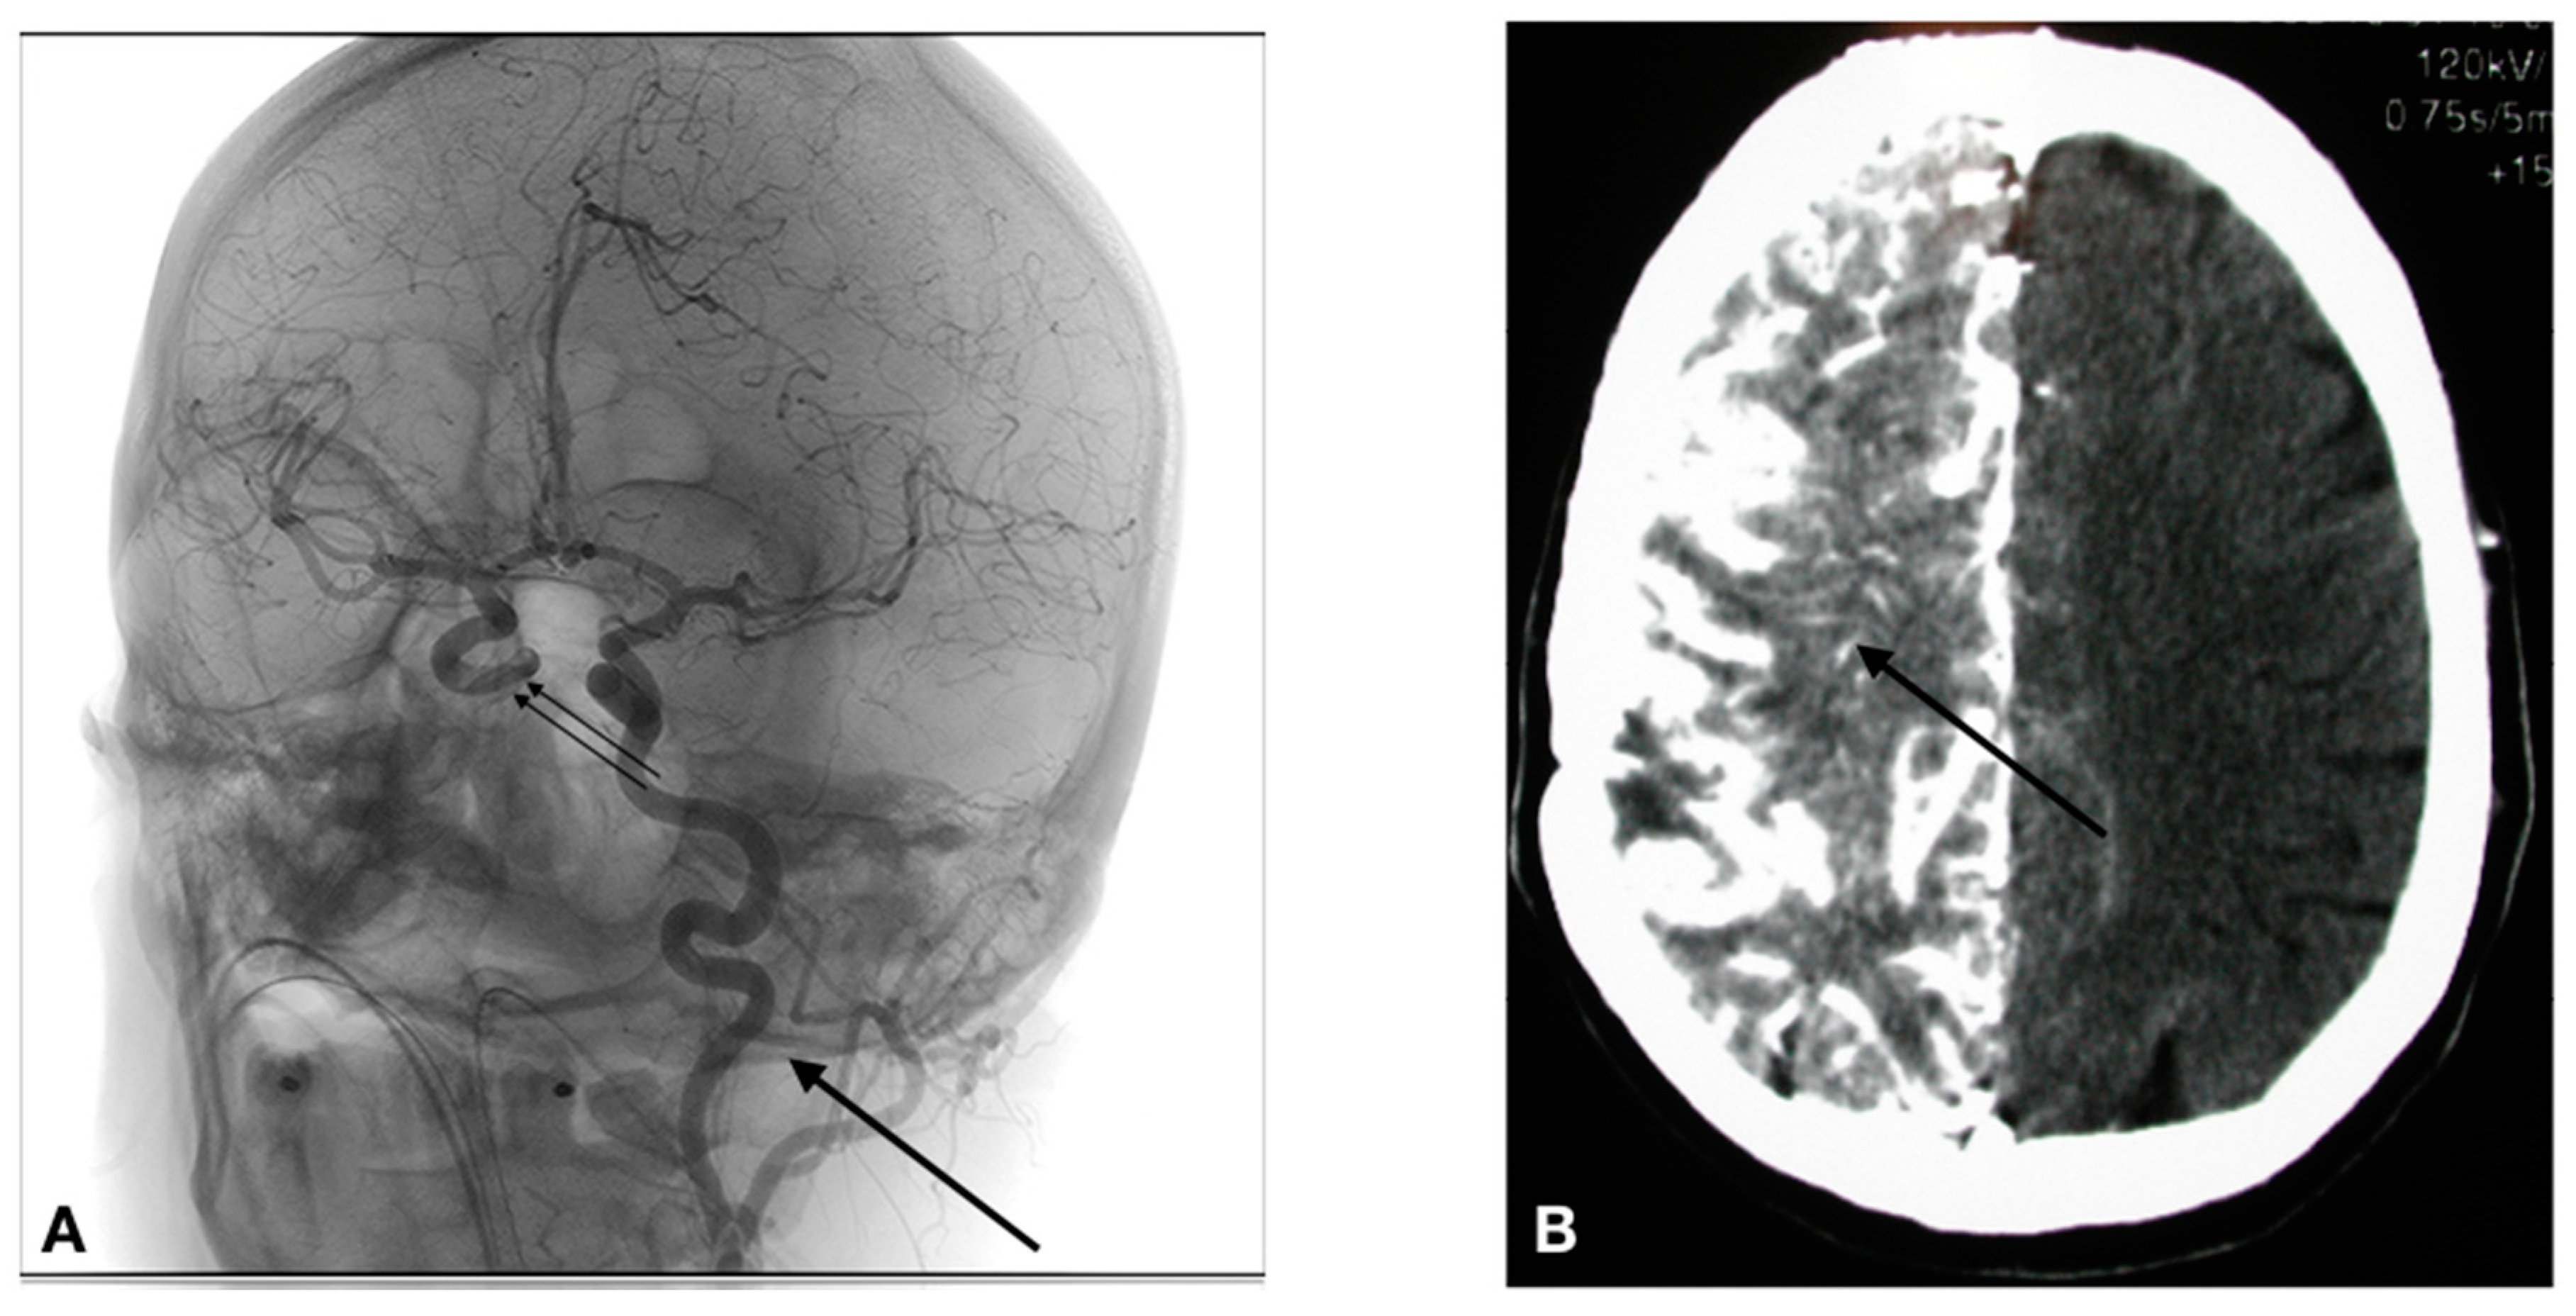

The access to the arterial system is obviously accomplished differently in humans. The human cerebral arterial system is organized in such a way that there basically are 4 major arteries responsible for the brain irrigation (2 carotids, and 2 vertebral arteries). The vascular anatomy can be variable from one individual to another, and thus the precise anatomy must be determined during the first treatment session by a formal cerebral angiography. If a lesion covers more than one vascular distribution, or if there are multiple lesions, the treatment is delivered by equally splitting the chemotherapy dose in the different distributions (vessels) involved. Parameters such as catheter placement, dilution, and rate of infusion are all standardized. In the human, the arterial system is accessed via a percutaneous transfemoral puncture. Once accessed, the catheter is navigated in the arterial system using radiological imaging (fluoroscopy). As shown in Figure 4A, the catheter has been placed in the left carotid artery, and a contrast infusion shows the distribution of this vessel.

1. Selective catheterization is performed via percutaneous transfemoral puncture of the left internal carotid artery, right internal carotid artery, left vertebral artery or right vertebral artery. The tip of the catheter is positioned at the C2-C3 vertebral level in the carotid (Figure 4), or at the C6-C7 vertebral level in the vertebral artery.

3. In the case of a BBBD: BBBD procedures require general anesthesia. Hence, after general anesthesia with Propofol, we proceed to a selective catheterization via percutaneous transfemoral puncture of the treated artery. We then determine the individual rate of infusion of Mannitol. We use iodinated contrast injection and fluoroscopy to establish, for each patient, the ideal infusion rate; it is the rate that will fill the entire vessel distribution, without producing significant reflux in the common carotid artery. Once established (usually between 3 and 6 cc/s × 30 s), the patient is prepared for the hemodynamic repercussions of the procedure. Indeed, the osmotic disruption is a physiologically stressful procedure. It can induce focal seizures in 5% of procedures. It can also trigger a vaso-vagal response with bradycardia and hypotension. In order to prevent the occurrence of these adverse effects, the following medications are administered just prior to the disruption: Diazepam 0.2 mg/kg IV (maximum dose = 10 mg), and Atropine IV, titrated to increase heart rate 10–20% from baseline (0.5–1 mg). We then proceed to the BBBD, after which IA infusion of chemotherapy is accomplished. Figure 4B shows the repercussion of BBBD on delivery. In this image, an IV contrast material was infused shortly after the BBBD (within 5 min), showing a diffuse penetration of the contrast compound in the brain parenchyma (arrow).

Figure 4. (A) Catheter placement in a glioblastoma patient treated for BBBD in the left carotid artery (arrow). An iodine contrast was infused, opacifying the left carotid distribution, as well as the contralateral carotid (double arrow) via the polygon of Willis. (B) The image produced by a BBBD of the right carotid artery on a computed tomography (CT) scan in a patient afflicted by a primary central nervous system (CNS) lymphoma after an infusion of iv iodine contrast. As can be appreciated, the whole hemisphere is bathed by the contrast, an evidence by the fact that the BBB is breached.